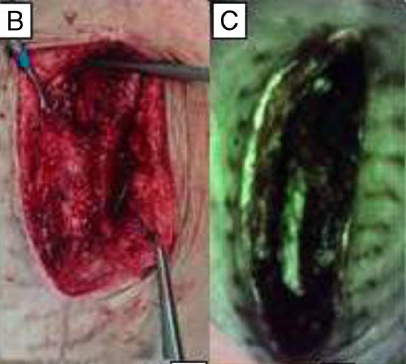

Multidisciplinary Strategies With Real-Time Fluorescence Images and Negative Pressure Wound Therapy to Manage Organ/Space Surgical Site Infection in Transplanted Kidneys

Chen, CH et al. Annals Plastic Surgery 2023

Bacterial fluorescence imaging as a predictor of skin graft integration in burn wounds

Hanson-Viana, E. et al. Burns 2024